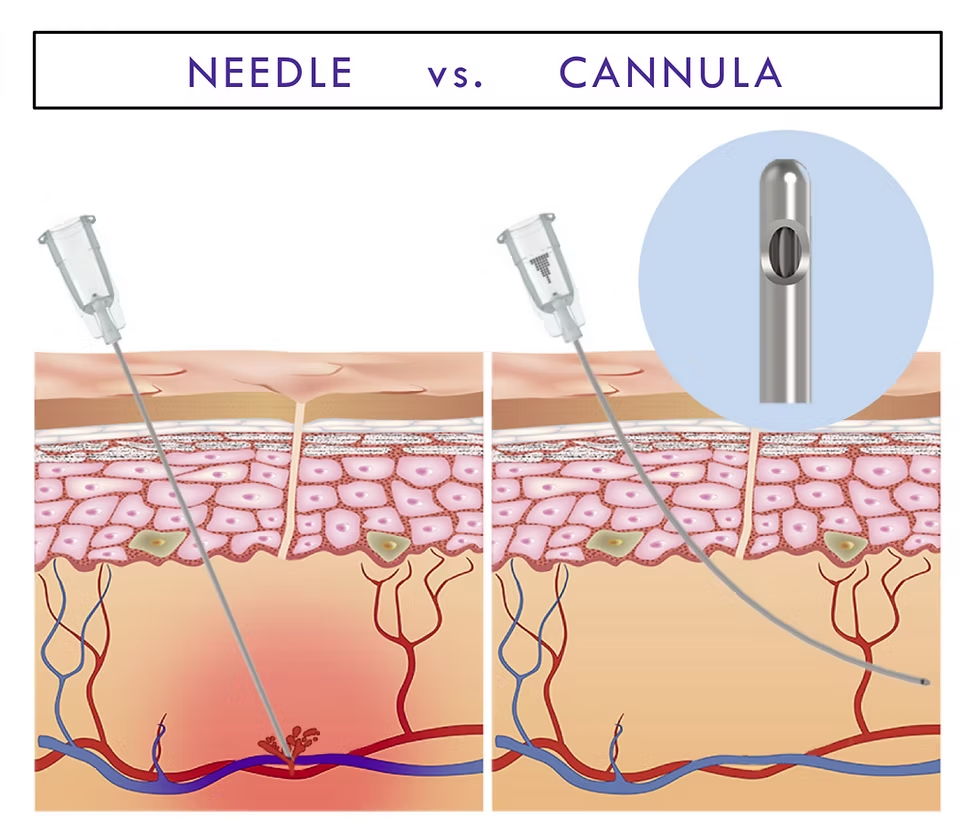

To extract & collect the fat, surgeons use liposuction with a blunt cannula in a 2-3mm cut created on your body. The cannula is moved back & forth to loosen the fat so it can be removed evenly. This movement looks really rough but usually doesn’t hurt. The area is injected with lidocaine/a numbing agent before this process occurs.

Using a cannula, you’re able to evenly spread out the microdroplets of fat through different areas, the logic behind injecting microdroplets should be obvious, the less you’re injecting at once the less likely you are to inject a large enough amount to block off vessels.

To extract & collect the fat, surgeons use liposuction with a blunt cannula in a 2-3mm cut created on your body. The cannula is moved back & forth to loosen the fat so it can be removed evenly. This movement looks really rough but usually doesn’t hurt. The area is injected with lidocaine/a numbing agent before this process occurs.

Using a cannula, you’re able to evenly spread out the microdroplets of fat through different areas, the logic behind injecting microdroplets should be obvious, the less you’re injecting at once the less likely you are to inject a large enough amount to block off vessels.